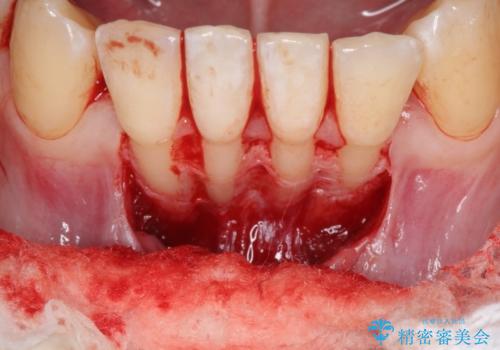

下顎前歯の歯肉退縮 結合組織を用いた根面被覆

- 歯肉退縮を主訴に来院された患者様です。

口蓋から結合組織を採取して、根面被覆を行いました。

十分な根面被覆を達成で患者様にも満足していただけました。